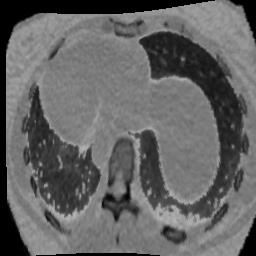

In clinical practice, well-aligned multi-modal images, such as Magnetic Resonance (MR) and Computed Tomography (CT), together can provide complementary information for image-guided therapies. Multi-modal image registration is essential for the accurate alignment of these multi-modal images. However, it remains a very challenging task due to complicated and unknown spatial correspondence between different modalities. In this paper, we propose a novel translation-based unsupervised deformable image registration approach to convert the multi-modal registration problem to a mono-modal one. Specifically, our approach incorporates a discriminator-free translation network to facilitate the training of the registration network and a patchwise contrastive loss to encourage the translation network to preserve object shapes. Furthermore, we propose to replace an adversarial loss, that is widely used in previous multi-modal image registration methods, with a pixel loss in order to integrate the output of translation into the target modality. This leads to an unsupervised method requiring no ground-truth deformation or pairs of aligned images for training. We evaluate four variants of our approach on the public Learn2Reg 2021 datasets \cite{hering2021learn2reg}. The experimental results demonstrate that the proposed architecture achieves state-of-the-art performance. Our code is available at https://github.com/heyblackC/DFMIR.